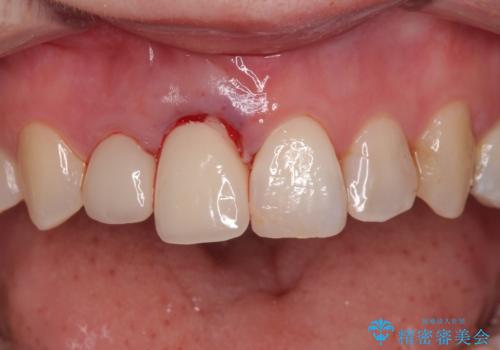

- 前歯のセラミッククランが外れてしまったとのことで来院された患者様です。

診察をしたところ、歯根に縦破折が認められ、抜歯が必要と判断されました。

抜歯、インプラント埋入、仮歯の装着が同時に可能な1DAYインプラントが適用可能と判断されたため、インプラントによる補綴治療を行うこととしました。